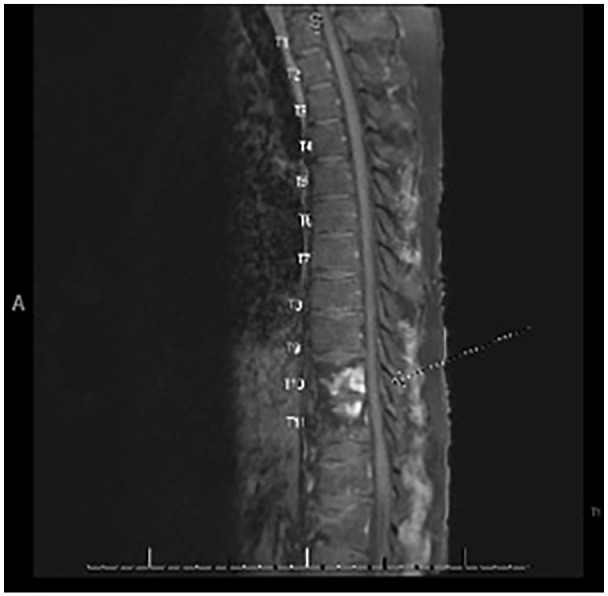

Co-infection with Mycobacterium tuberculosis and Aspergillus in an immunocompetent host is rare but can occur. In this case, we present a patient with central nervous system tuberculosis (TB) and biopsy-proven spinal co-infections with TB and Aspergillosis. We highlight the complexities of treating a TB-Aspergillosis co-infection given drug-drug interactions between standard therapy for both conditions. Using susceptibilities for the Aspergillus and carefully monitoring drug levels of the antifungal agents, we were able to optimally treat the co-infection. This patient was ultimately discharged on isoniazid 1200 mg (15 mg/kg) daily, levofloxacin 750 mg daily, rifabutin 450 mg daily, and posaconazole 300 mg twice daily with a tentative plan to treat for at least 1 year with close outpatient follow-up. This case can serve as a guide for other providers who need to treat cases of TB and Aspergillosis co-infection by learning from our experience and paying attention to potential pitfalls.